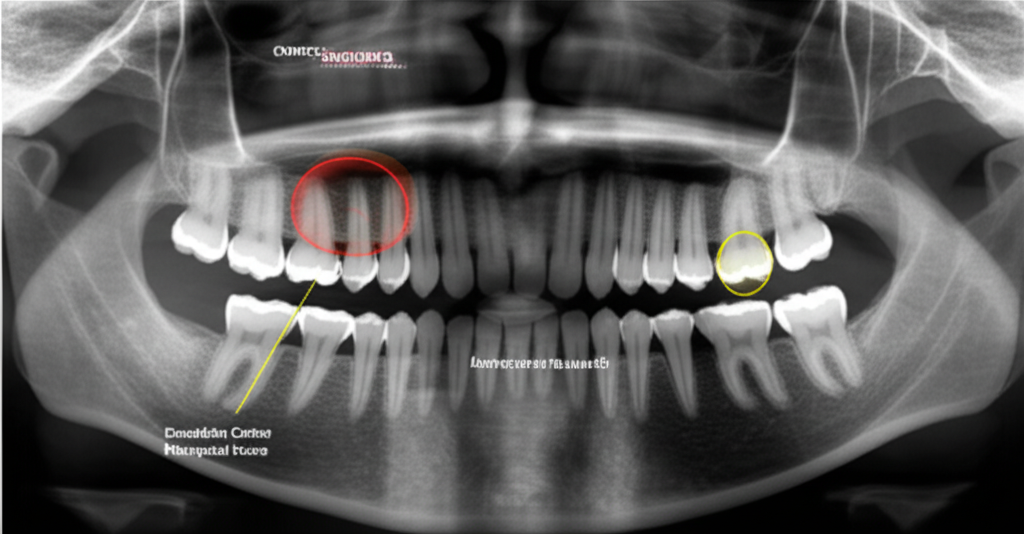

Our AI models can identify and classify multiple dental conditions simultaneously with clinical-grade accuracy.

Comprehensive analysis reports with confidence scores and visual annotations for each finding.